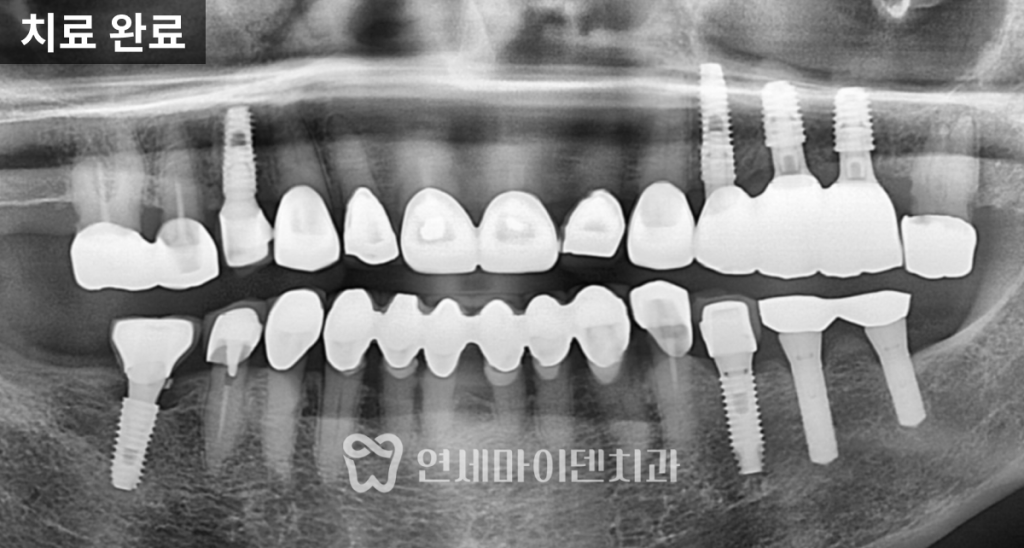

치아교정·임플란트 협진 케이스를 설명드리겠습니다.초진 상태

초진 파노라마 사진에서

오래전 6번 어금니가 발치된 상태였습니다.그 뒤쪽에 있던 7번, 그리고 사랑니가

앞쪽으로 상당히 많이 쓰러져 있었습니다.

원래 6번과 7번은

크기가 거의 비슷해야 하는데,쓰러지면서

임플란트가 들어가야 할 공간이

앞 치아보다도 더 좁아진 상태였습니다.이 상태에서 임플란트를 바로 진행하면

정밀한 힘 조절이 필요합니다.치아교정 7개월차: 공간 확보

약 7개월이 지나면서

쓰러졌던 7번 치아는 눈에 띄게 세워졌고

임플란트가 들어갈 수 있는 공간이

목표로 해야 합니다.임플란트 식립과 마무리

공간 확보 후

임플란트를 정확한 위치에 식립했습니다.임플란트가 뼈와 안정적으로 결합되는 동안

교정을 병행해 공간을 유지했고,최종적으로 교합 간섭 없이

자연스러운 씹는 기능을 회복했습니다.

교정 전과 비교하면

임플란트 공간은 체감상 두 배 이상 확보되었고

다른 치아들의 불필요한 이동 없이

치료가 안정적으로 종료되었습니다.협진이 중요한 이유